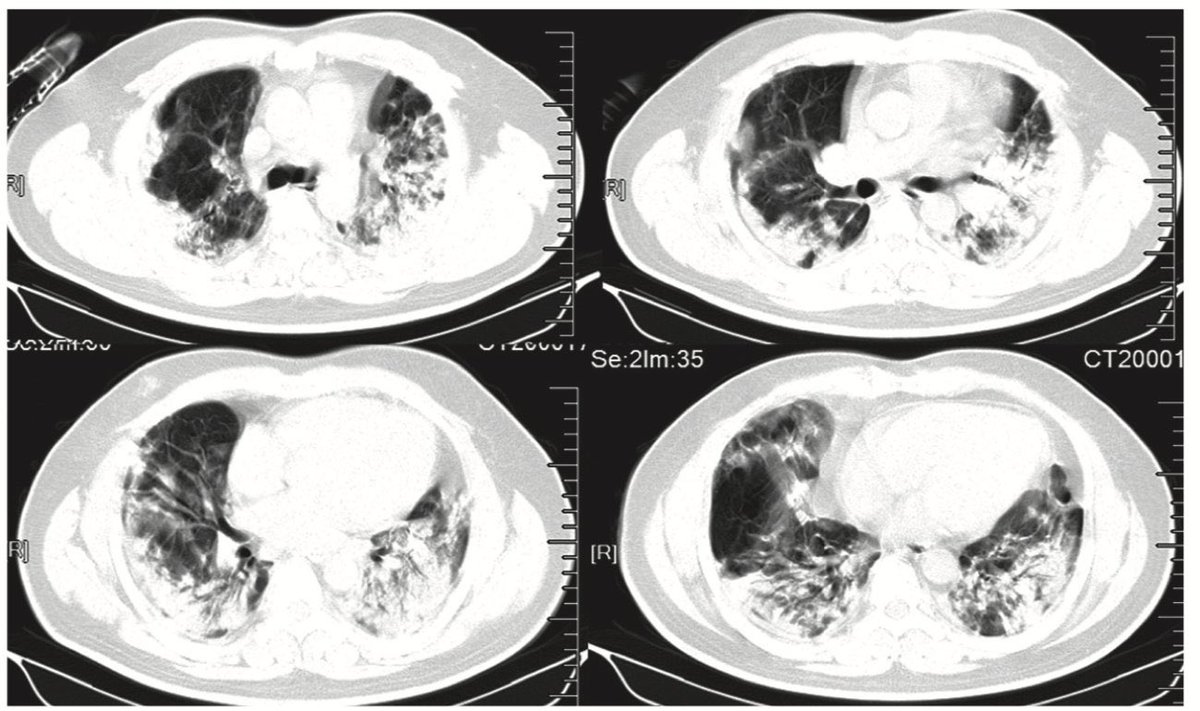

تشير الخصائص السريرية لأول ٤١ مريض الى ان #كورنا الجديد لديه بداية شديده مع حمى وسعال وألم عضلي مصحوب بضيق تنفس، النتائج من الاشعه الصدريه تشير الى التهاب رئوي حاد يكون اقل حده مع منهم تحت ٦٠ سنه وأكثر حده مع من تجاوز عمره ٦٠ سنه

في هذه الدراسه، 75% من المرضى الذين يعانون من #كورنا يصاحبهم التهاب #رئوي، 20% منهم كان حاد، 4% فقط احتاجو تنفس صناعي، تلقت الغالبية العظمى منهم الادويه المضادة للفيروسات ومضادات الميكروبات